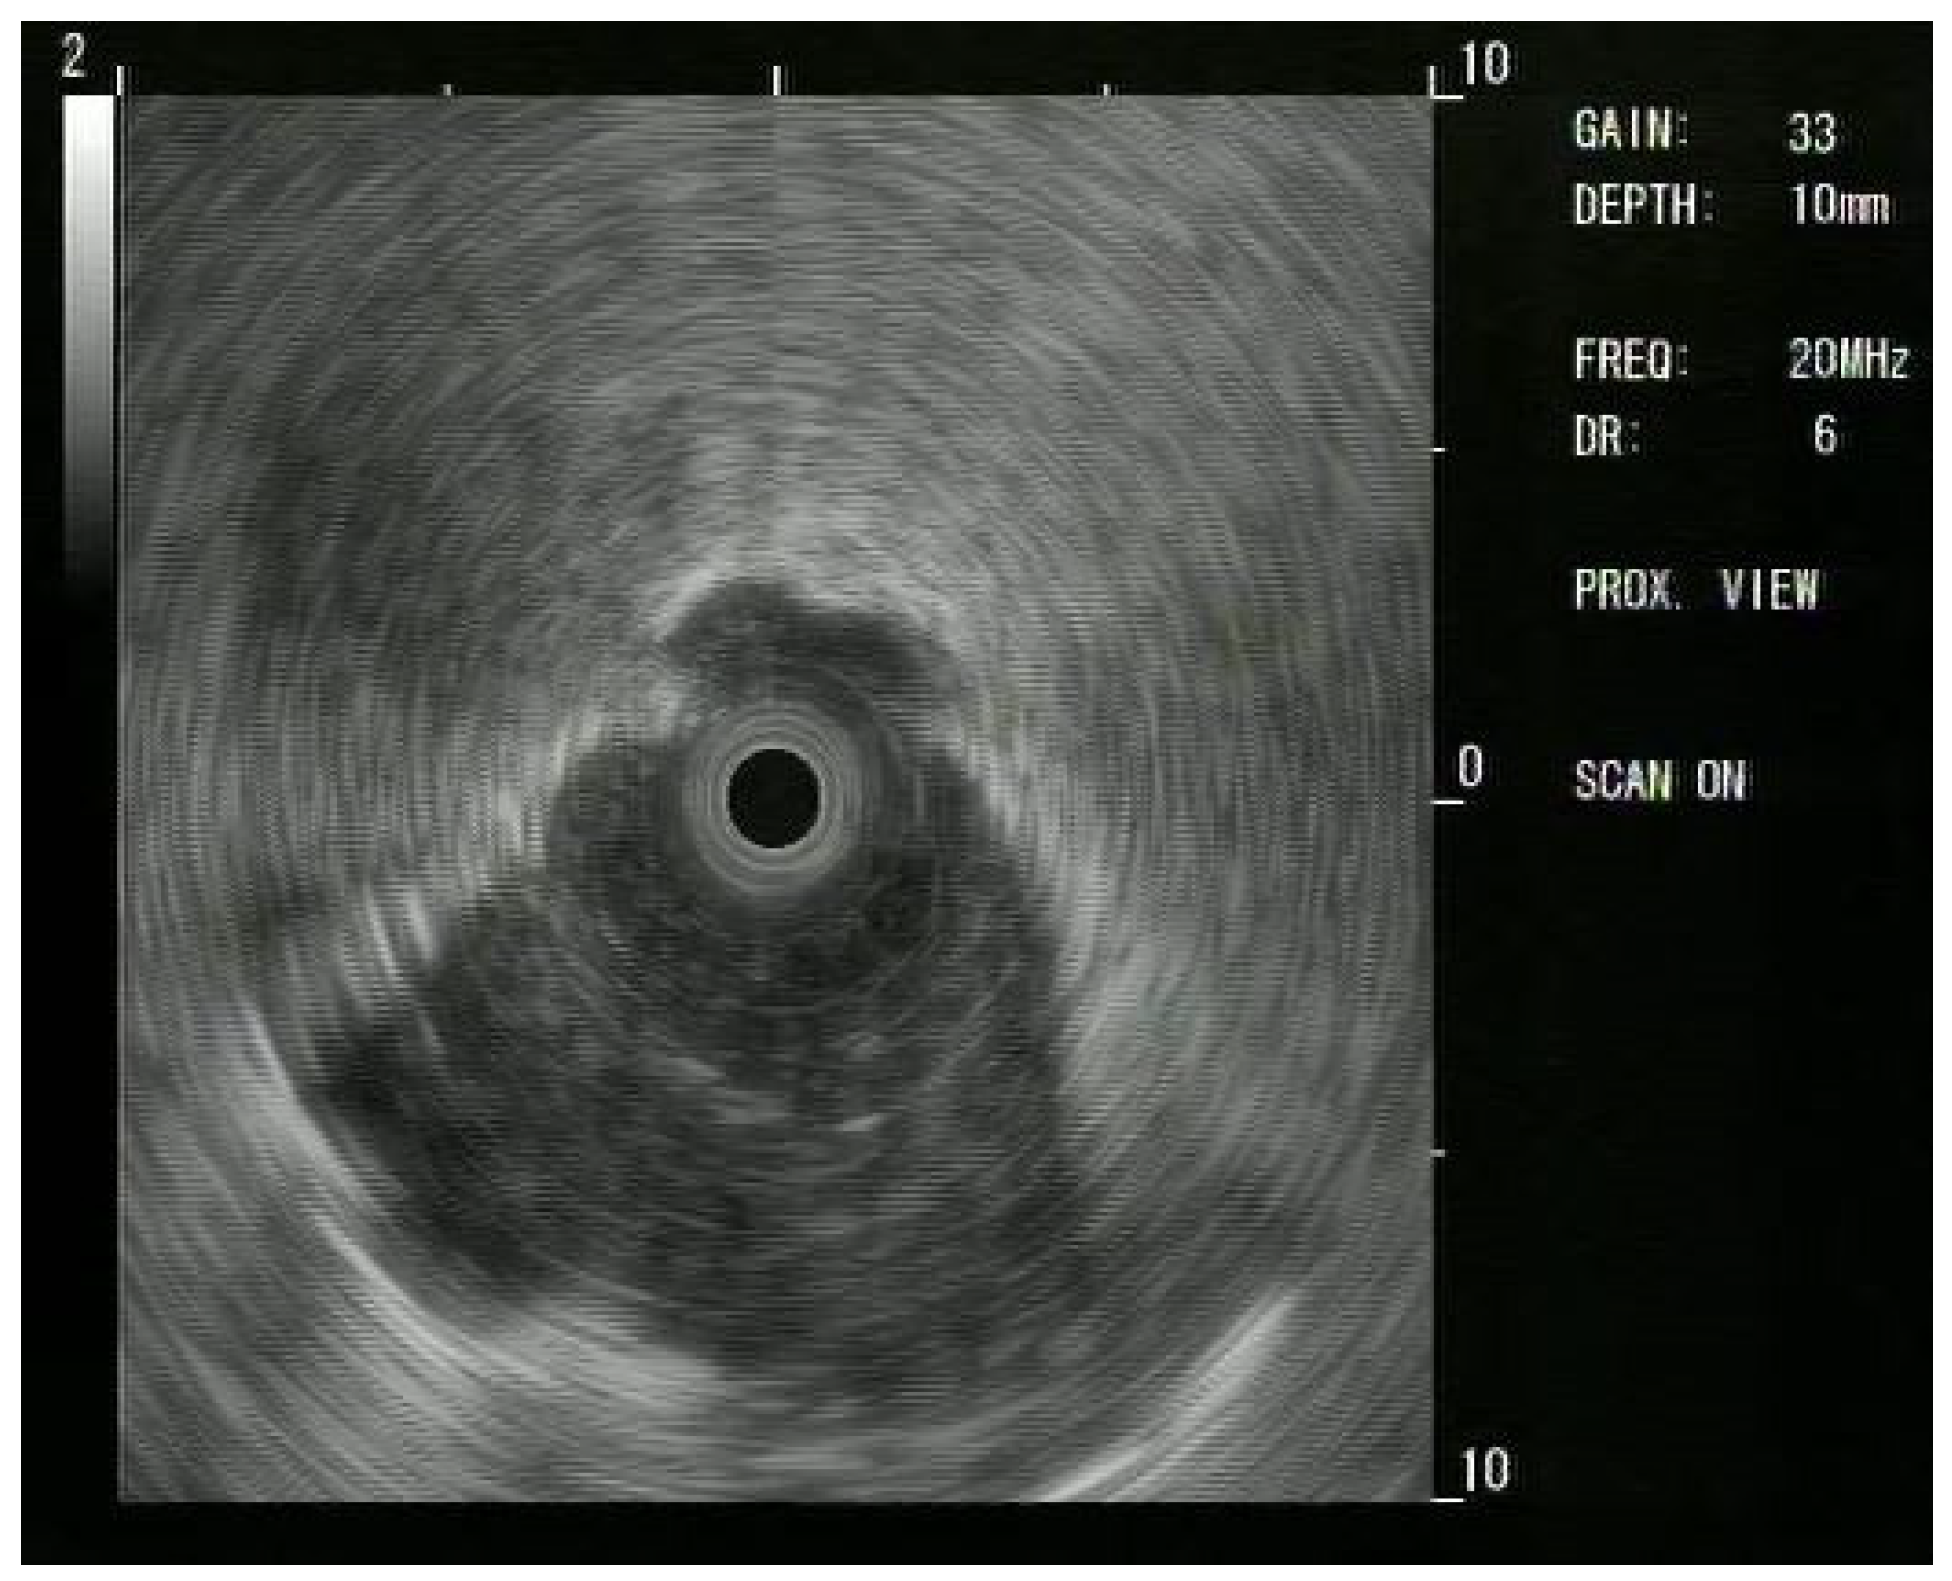

Figure 3. Radial EBUS (R-EBUS) confirmation of a PPL; the use of R-EBUS helps the procedure guiding the transbronchial biopsy. The consolidative pattern in the lower part of the image confirms that a nodule is outside the bronchus.

Bronchoscopy with a TB was performed under moderate sedation using our institution’s standard protocol. Patients were monitored during all parts of the procedure and sedation was titrated to the patient’s comfort and ability to follow commands. A TB was used (EB-710P, Fujifilm, Tokyo, Japan), shown in Figure 1. Target tool identification was used at the discretion of the bronchoscopist, depending on the endoscopic finding and chest CT scan imaging (R-EBUS, R-EBUS + fluoroscopy, none), shown in Figure 2 and Figure 3. The target lesion was sampled with 2.00 mm forceps (Endojaw FB-211D, 1.9 mm, Olympus Medical Systems Corp., Tokyo, Japan) or with a conventional TBNA needle (Wang® Transbronchial cytology needle MW-122, Conmed, Utica, NY, USA).

Since these results, Ips have moved to using R-EBUS: a thin, flexible catheter with a rotating ultrasound transducer that produces a 360-degree (“radial”) image; the catheter easily passes through the working channel of the scope. This provides a 360-degree view in a 2D plane [12].